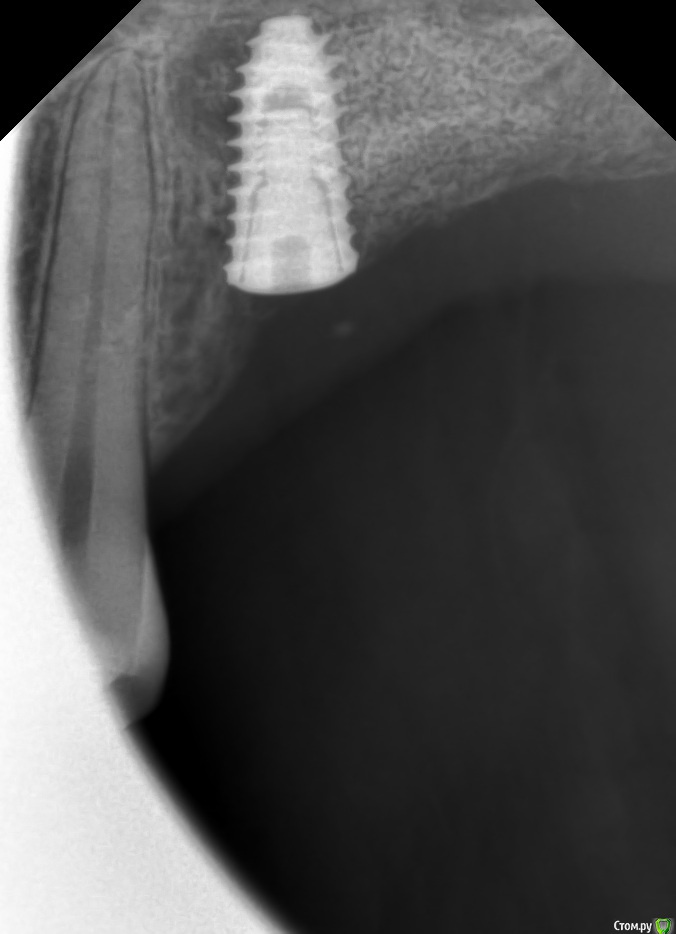

kamranchick Опубликовано 23 февраля, 2018 Поделиться Опубликовано 23 февраля, 2018 Спасибо,через 6 мес буду ставить 1 имплант в область 2.6.Да, вижу, что получился зиккурат, я еще плохо себе представляю как рассчитать соотношение высоты к основанию объёма,для наметки высоты я засверливаюсь на 3мм ниже будущей "вершины" или "будущего дна пазухи", не понимаю где будут границы основания.и старайтесь доводить до медиальной стенки. 1 Ссылка на комментарий

Sampson Опубликовано 24 февраля, 2018 Поделиться Опубликовано 24 февраля, 2018 (изменено) А сразу имплант что не поставили?При планировании было желание рискнуть, попробовать,но опыта пока мало, суммарно я поставил 20 имплантов. Первый синус с установкой, так вообще бывает? Изменено 24 февраля, 2018 пользователем Sampson Ссылка на комментарий

kamranchick Опубликовано 22 апреля, 2018 Поделиться Опубликовано 22 апреля, 2018 (изменено) Пациент после открытого синуса 2 месяца прошло, какие мысли коллеги? что делать, ничего не беспокоит, во рту все стабильно. Изменено 22 апреля, 2018 пользователем kamranchick Ссылка на комментарий